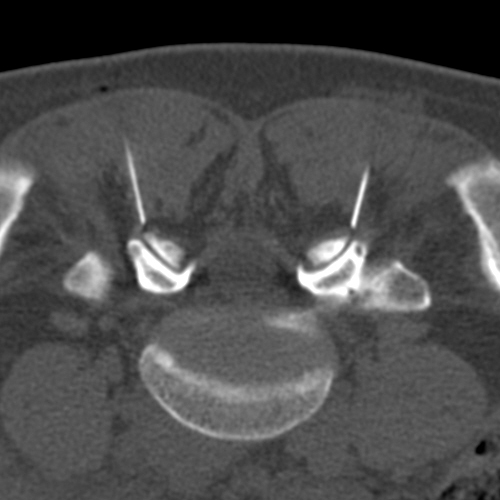

Die Behandlung wird grundsätzlich in örtlicher Betäubung mit sehr feinen Nadeln vorgenommen. Der Patient liegt auf dem Bauch auf dem CT-Tisch. Zur genauen Höhenlokalisation der Schmerzstelle wird auf den Rücken ein Metallstreifen geklebt. Ein so genanntes Topogramm, also eine Übersichtsaufnahme des entsprechenden Wirbelsäulenabschnittes wird angefertigt. Jetzt kann auf dem computertomographischen Schnittbild die Schmerzstelle lokalisiert werden. Auf dem Bearbeitungsmonitor können dann der exakte Eintrittspunkt der Nadel, der Winkel und die Tiefe, in der gespritzt werden soll, ermittelt werden. All diese Parameter werden anschließend mit einem Laserpunkt auf dem Patienten dargestellt. Gefolgt von einer örtlichen Punktion nach steriler Säuberung der Haut kann die feine Punktionsnadel, die eine millimetergenaue Skalierung aufweist, am Schmerzpunkt platziert werden. Es folgt die Kontrollaufnahme zur Dokumentation der exakten Nadellage.

An die Wirbelgelenke wird ein langwirksames Betäubungsmittel gespritzt. Zur Optimierung der Wirkung und Verträglichkeit setzen wir als entzündungshemmende Präparate zusätzlich Retard-Corticosteroide ein, die verzögert über längere Zeit am Wirkort freigesetzt werden. Bei gutem mehrmaligem Ansprechen auf solche Facettenspritzen kommt gelegentlich auch hochdosierter Alkohol als Verödungsmittel zum Einsatz. An Nervenwurzeln wird fast ausschließlich ein eiweißgelöstes Depot-Corticosteroid gespritzt. Sinn dieses Medikamentes ist, die Entzündungsreaktion im Nerv abzudämpfen und die Schwellung aufzuheben, so dass bei Entspannung der Nervenwurzel der Schmerz verschwindet oder sich abschwächt.

Alle oben dargestellten Aufnahmen respektive Therapien wurden im Bereich der Lendenwirbelsäule bzw. am Kreuzbein vorgenommen. In gleicher Art und Weise führen wir auch im Bereich der Brust- und Halswirbelsäule Infiltrationen durch. Einzige Ausnahme ist, dass hier keine epiduralen Spritzen gesetzt werden, da die Verletzungsgefahr des Rückenmarks in diesem Bereich nicht hoch ist.